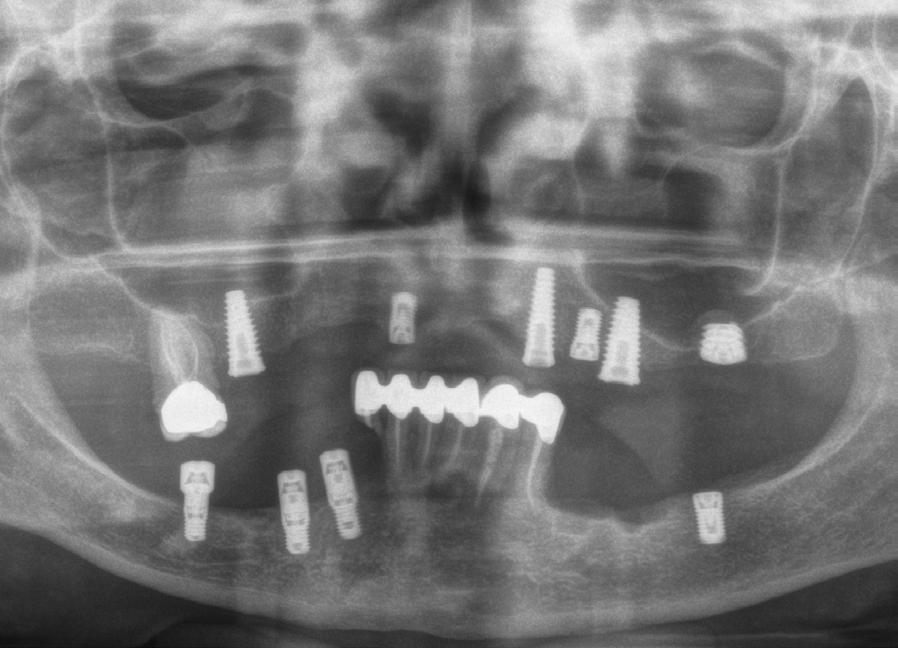

Figura 1. Radiografía inicial del caso donde observamos varios implantes con periimplantitis en el arco superior e inferior en diferentes estadios, incluso un implante que ya se ha perdido en la zona del incisivo lateral superior izquierdo y en el cuarto cuadrante.

Figura 6. Radiografía postoperatoria tras las explantaciones y regeneración con PRGFENdoret de las zonas afectadas donde no era posible colocar nuevos implantes en la misma fase quirúrgica, así como colocación de otros implantes para iniciar la renovación del caso. Se mantuvieron tres implantes superiores provisionalmente para soportar la prótesis provisional.

Figura 9. Radiografía con las prótesis de carga inmediata.

Figura 12. Radiografía final con las prótesis, a los 3 años de seguimiento, con la estabilidad de todos los implantes, sin nuevas pérdidas óseas asociadas.